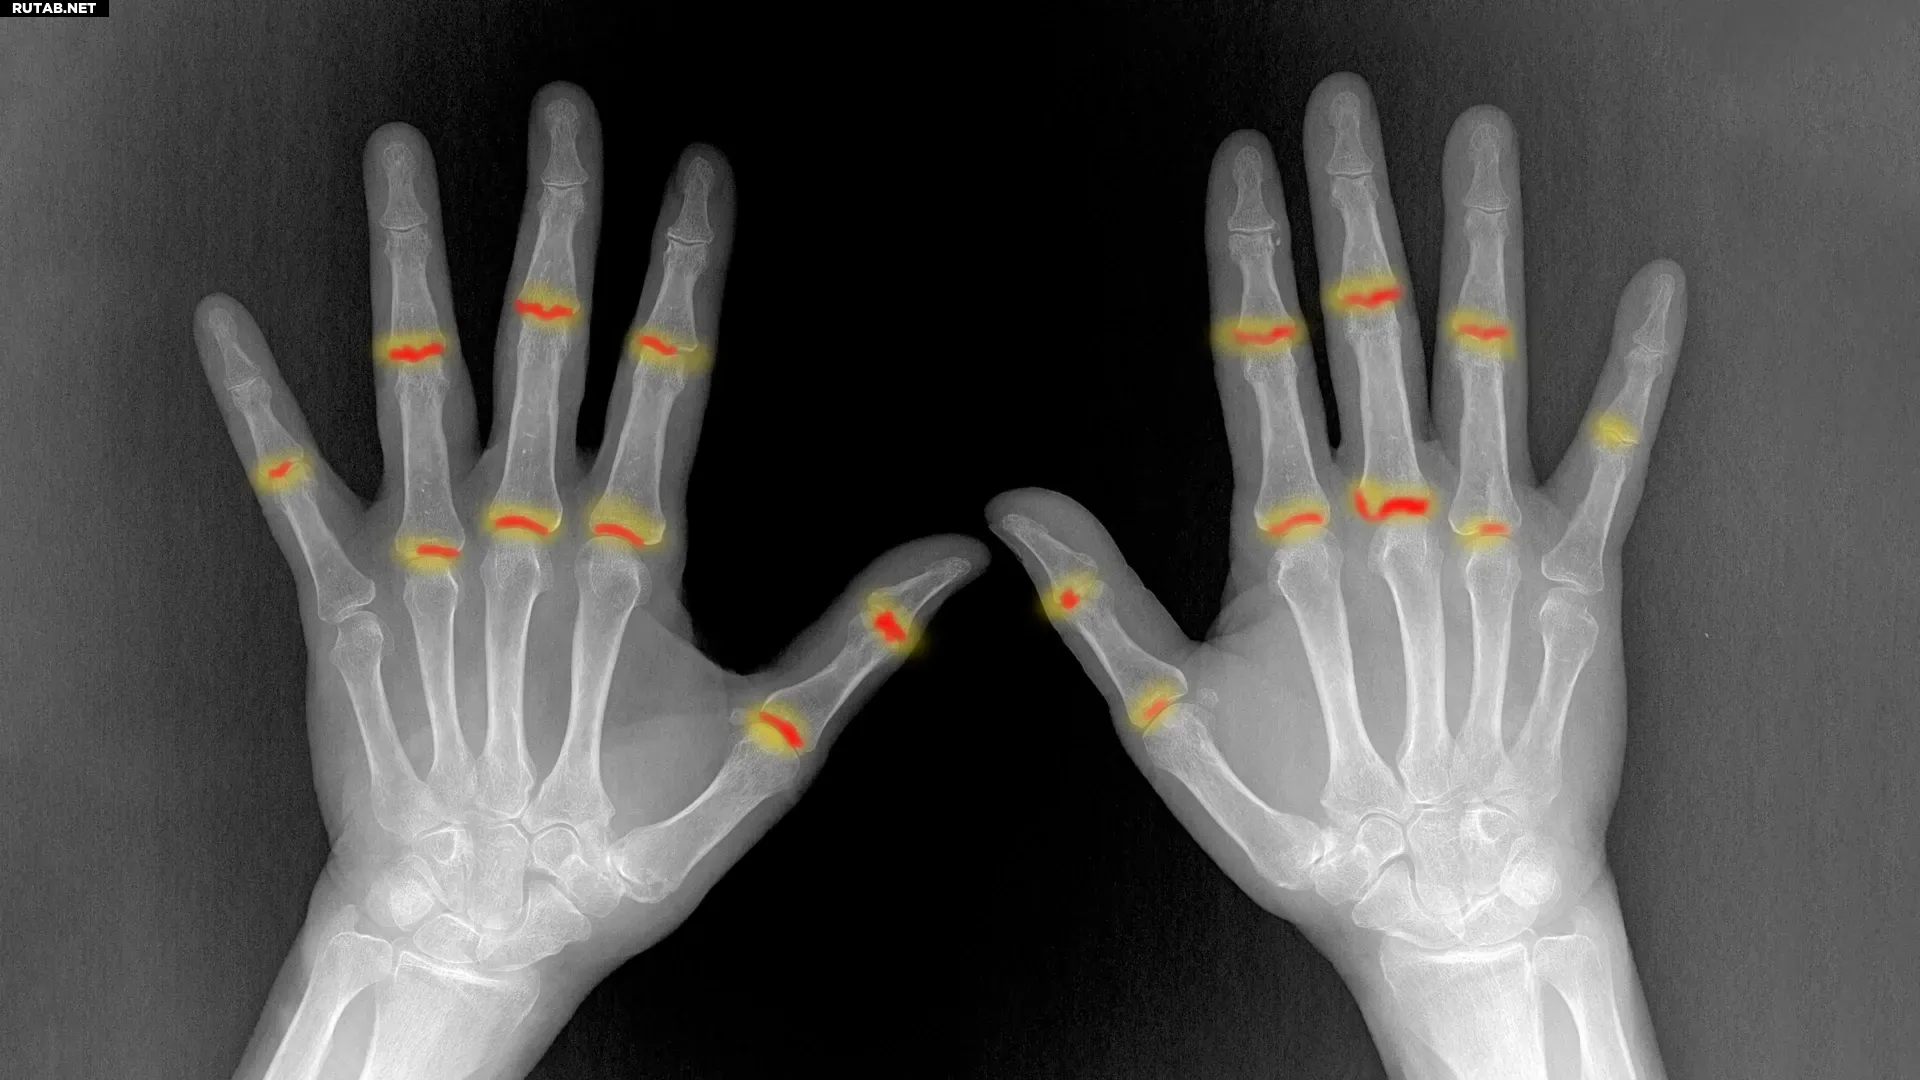

Исследователи из Университетской клиники Эрлангена (FAU) обнаружили механизм, по которому псориаз может перерасти в псориатический артрит. Примерно у 20-30% пациентов с псориазом развивается это болезненное воспаление суставов, способное привести к их необратимому повреждению.

Учёные выявили, что при псориазе в коже образуются особые иммунные клетки-предшественники. Эти клетки способны мигрировать через кровоток и попадать в суставы. Однако их присутствия недостаточно для начала воспаления.

Важным открытием стало то, что эти мигрирующие иммунные клетки можно обнаружить в крови ещё до начала воспаления суставов. Это открывает возможность раннего выявления пациентов с высоким риском развития артрита.